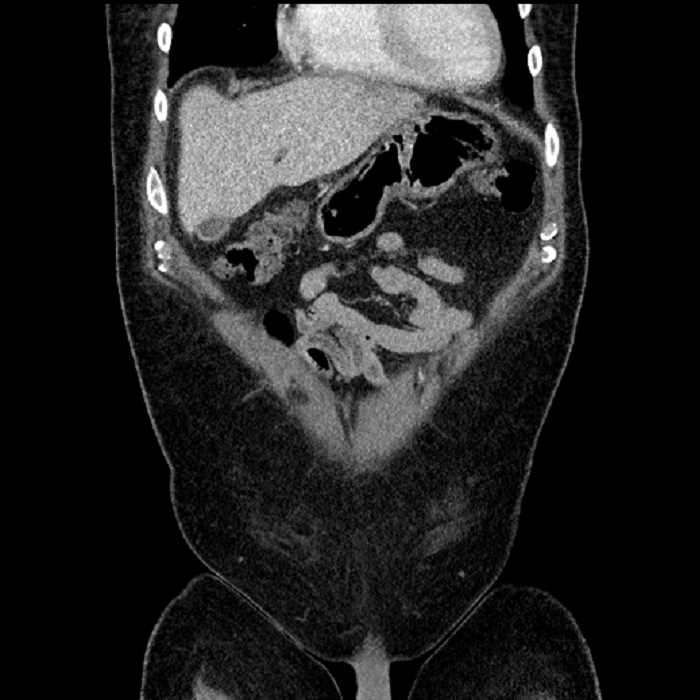

• Large fluid density structure in hepatic segments 7 and 8 measuring 10 x 7 x 7 cm with internal septation and circumferential ill-defined low density compatible with edema

• Peripherally enhancing subcapsular collections along the anterior margin of the left hepatic lobe measuring 3 x 1 cm and 2 x 1 cm

• Mild mural thickening of a segment of the sigmoid colon with adjacent fat stranding and a 1.5 cm fluid and gas collection along the tip of an inflamed diverticulum

• Loss of the normal fat plane between this collection and adjacent loops of small bowel, which demonstrate mural thickening

• High grade stenosis of the left common iliac artery, with the left internal and external iliac arteries remaining patent

Acute sigmoid diverticulitis complicated by a small contained perforation and a large abscess in the right hepatic lobe. Additional small subcapsular abscesses along the anterior margin of the left hepatic lobe.

Additionally, loss of the normal fat plane between the peridiverticular collection and adjacent thickened loops of small bowel raises the potential for an enterocolonic fistula.

High grade stenosis of the left common iliac artery. The left external and internal iliac arteries are patent.

Hepatic abscess showing the double target sign with low density internally surrounded by a thin inner enhancing rim (red arrow) and ill-defined outer low density rim (yellow arrow). Blue arrow indicates an internal septation. Red arrows: additional smaller subcapsular abscesses. Red arrow: focal contained perforation associated with diverticulitis.